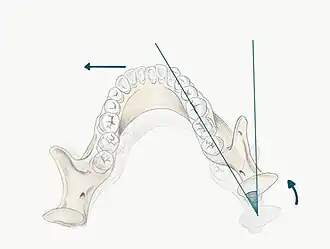

The patient may be guided into CR using one of the follow methods;

- Bimanual manipulation- manipulating the patient's condyles so they are in CR

- The operator should lightly rest their fingers along the inferior border of the mandible and their thumbs should lie lightly on the anterior aspect of the chin

- When the patient is relaxed place light downward pressure on the chin and light upward pressure under the angle of the mandible

- Deprogramme the jaw by guiding the opening and closing of the jaw and once the patient is relaxed, ask them to close gently and stop when they feel teeth first contacting

- Chin point guidance- one hand is used to apply pressure to the chin guiding the chin posteriorly with some force

In some patients it may be difficult to guide the mandible into CR, for example in those with muscle tension, muscle splinting, occlusal disharmony or parafunctional habit. For these patients a Lucia Jig or deprogramming appliance can be constructed at chair-side.